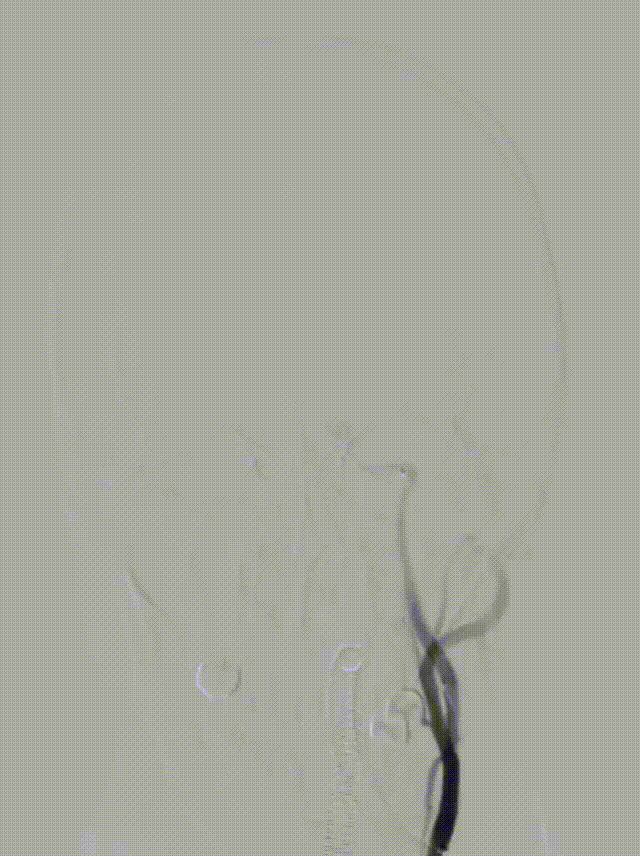

将6F Oneering®远端通路导管自颈段负压抽吸至左侧大脑中动脉M1段,抽吸出大量血栓。行路图提示颈内动脉及大脑中动脉通畅。

术后造影:可见左侧颈内动脉通畅,大脑前动脉不显影,因患者前交通动脉开放,未处理。